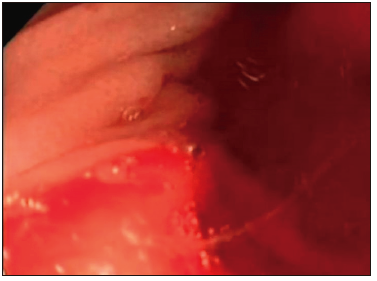

Los resultados obtenidos en nuestro estudio coinciden con los observados en otras

publicaciones,7-8 donde la ingesta de cuerpos extraños fue la causa más frecuente de urgencia

endoscópica en pediatría, y representaron el 83% de los casos en nuestra serie. Los síntomas descriptos

cuando el CE se encontraba en una ubicación más proximal fueron sialorrea, náuseas y sensación de ahogo. Por

el contrario, cuando el cuerpo extraño se hallaba en una ubicación más distal, los síntomas podían ser menos

evidentes, como dolor retroesternal, o con ausencia de síntomas. Todos los cuerpos extraños fueron extraídos

por vía endoscópica, excepto en los dos casos de bezoares, en los cuales se intentó inicialmente reducir su

tamaño mediante diferentes métodos, como cortándolos para su extracción con pinzas o canastillas (Foto

1).

Sin embargo, ante la falta de éxito, se decidió realizar su extracción por vía quirúrgica, con

éxito y sin complicaciones posteriores.

Foto 1. Tricobezoar hallado durante la endoscopía en una niña de 14 años a la cual se

le realizaron distintos procedimientos para minimizarlo, con resultados negativos. Se lo extrajo de manera

quirúrgica